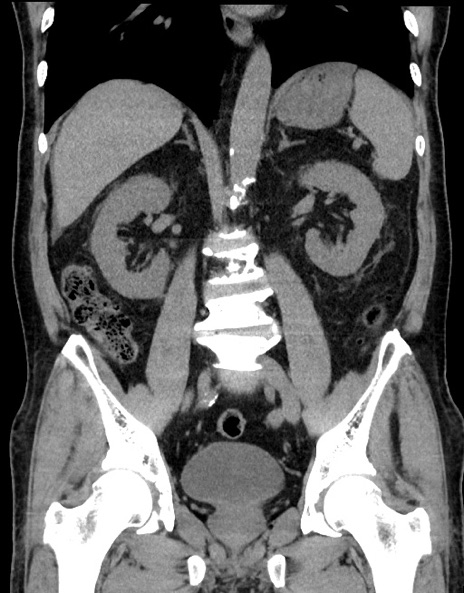

症例15(冠状断像)

【症例】70歳代男性

【主訴】腹痛

【現病歴】今朝から腹痛あり。全体的に痛い。特に左上の方。排ガスが今日はない。冷や汗が出る。

【既往歴】直腸癌術後

【身体所見】左側腹部〜上腹部に圧痛あり。腹膜刺激症状明らかなではない。軽度反跳痛。左下腹部に術後瘢痕あり。

【データ】WBC 7700、CRP 0.02